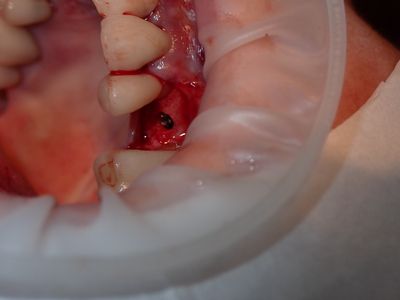

NSankhyan - immediate 13, impls 1121 and 25 with grafting

13 exo, loss of labial plate, implant placed buccal region grafted with sticky bone and collagen membrane soaked in prf fluid. 11/21 limited Labial-palatal width of bone, ridge split to 5mm, osteotomies prepared to about 2mm, remainder with densah drills, implants placed with ample bone, buccal grafted with same sticky bone. densah drills used for apical portion of 25 implant, soft bone, implant placed